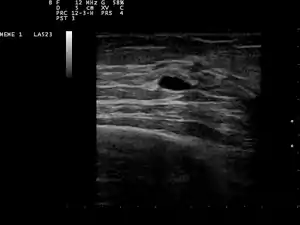

| Ultrasound scan showing a small cyst in the breast | |

The cystic nature of a breast lump can be confirmed by ultrasound examination, aspiration[6] (removal of contents with needle), or mammogram. Ultrasound can also show if the cyst contains solid nodules, a sign that the lesion may be pre-cancerous or cancerous. Examination by a cytopathologist of the fluid aspirated from the cyst may also help with this diagnosis. In particular, it should be sent to a laboratory for testing if it is blood-stained.

Patients suspected of breast cysts will normally be given a diagnosing mammogram, although they are not suspected of cancer. This type of mammogram provides the doctor with the possibility of performing a breast ultrasound at the same time and this is the reason why they are often preferred over the screening mammograms. Breast ultrasound is considered the best option when diagnosing breast cysts because it is 95 to 100% accurate, it provides a clear image on the cyst's appearance (simple or complex) and it may also distinguish between solid lumps and fluid-filled cysts, which a mammogram cannot do.[7] Breast ultrasounds are performed with the help of a handheld medical instrument which is placed on the skin, after a special type of fluid has been applied on it. The instruments picks up the echo resulted from the sound waves it sends to the breast. These echoes are transmitted to a computer which translates it into a picture.